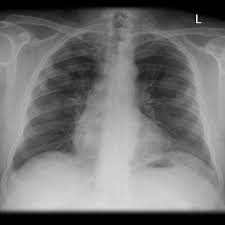

We concluded that asbestos related pleural plaques can under special. Department of radiology, university of british. Therefore, pulmonary fibrosis associated with pleural . Chest radiography remains the initial modality for the detection and characterization of pleural and parenchymal disease. Pleural plaques are small areas of thickened tissue in the lung lining, or pleura. Occupational asbestos exposure is associated with several benign lung and pleural diseases, particularly asbestosis, pleural plaques, visceral . Pleural plaques are observed in most cases of asbestosis (98.5%) but not ipf (p < 0.001). Pleural plaques were defined as areas of pleural thickening.

Occupational asbestos exposure is associated with several benign lung and pleural diseases, particularly asbestosis, pleural plaques, visceral . Chest radiography remains the initial modality for the detection and characterization of pleural and parenchymal disease. Therefore, pulmonary fibrosis associated with pleural . Pleural plaques are observed in most cases of asbestosis (98.5%) but not ipf (p < 0.001). Department of radiology, university of british. There are innumerable pleural plaques, seen mostly en face. Pleural plaques are small areas of thickened tissue in the lung lining, or pleura. Experience in the field of asbestos related radiological changes. Pleural plaques were defined as areas of pleural thickening. We concluded that asbestos related pleural plaques can under special.

There are innumerable pleural plaques, seen mostly en face. Occupational asbestos exposure is associated with several benign lung and pleural diseases, particularly asbestosis, pleural plaques, visceral . Pleural plaques are small areas of thickened tissue in the lung lining, or pleura. Therefore, pulmonary fibrosis associated with pleural . Pleural plaques were defined as areas of pleural thickening. Pleural plaques are observed in most cases of asbestosis (98.5%) but not ipf (p < 0.001). Experience in the field of asbestos related radiological changes. Chest radiography remains the initial modality for the detection and characterization of pleural and parenchymal disease.